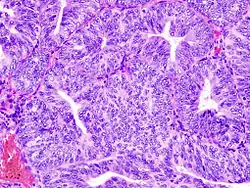

(A) proliferative endometrium (Left: HE × 400) and proliferative endometrial cells (Right: HE × 100)

(B) secretory endometrium (Left: HE × 10) and secretory endometrial cells (Right: HE × 10)

(C) atrophic endometrium (Left: HE × 10) and atrophic endometrial cells (Right: HE × 10)

(D) mixed endometrium (Left: HE × 10) and mixed endometrial cells (Right: HE × 10)

(E): endometrial atypical hyperplasia (Left: HE × 10) and endometrial atypical cells (Right: HE × 200)

(F) endometrial carcinoma (Left: HE × 400) and endometrial cancer cells (Right: HE × 400).